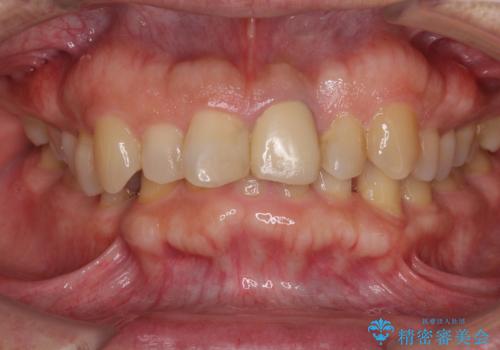

- 上下前歯のデコボコと下顎小臼歯の欠損によるスペースを気にして来院された患者様です。

下顎は左右1本ずつ小臼歯が欠損しており、右側にはやや大きな欠損がありました。

欠損により下顎歯列は相対的に小さく、上顎に深く咬みこんでしまうディープバイトとなっていました。